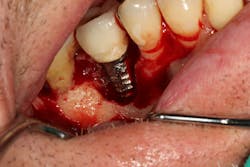

Figure 9: Initial presentation prior to crown lengthening

Figure 10: Immediate post-op hard- and soft-tissue crown lengthening with laser